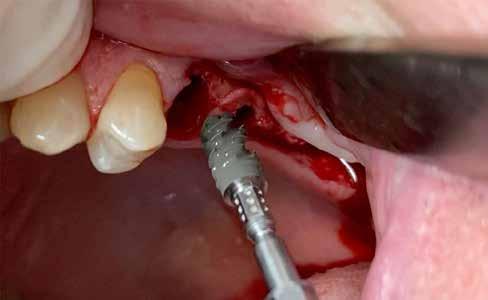

A részleges extrakció befejezése után következhet az implantátumágy preparálása a gyártó utasításai szerint (6.

kép). A bemutatott esetben Nobel Replace CC 4,3x13mm implantátumot helyeztünk be, amely a bukkális oldalon direkt kontaktusba került a megmaradt foggyökérdarabbal (7. kép). Az alveolus oldalfalai és a körszimmetrikius implantátum közötti hézag kitöltésére bovin eredetű xenograftot (Creos S xenogain) használtunk (8. kép). A hasonló

6. kép: Implantátum-ágy preparáció. 7. a–b. képek: Implantátum behelyezés. 8. kép: A behelyezett implantátum. 10. a–b képek: Azonnali ideiglenes korona készítése. 9. kép: Megfelelő primer stabilitás.